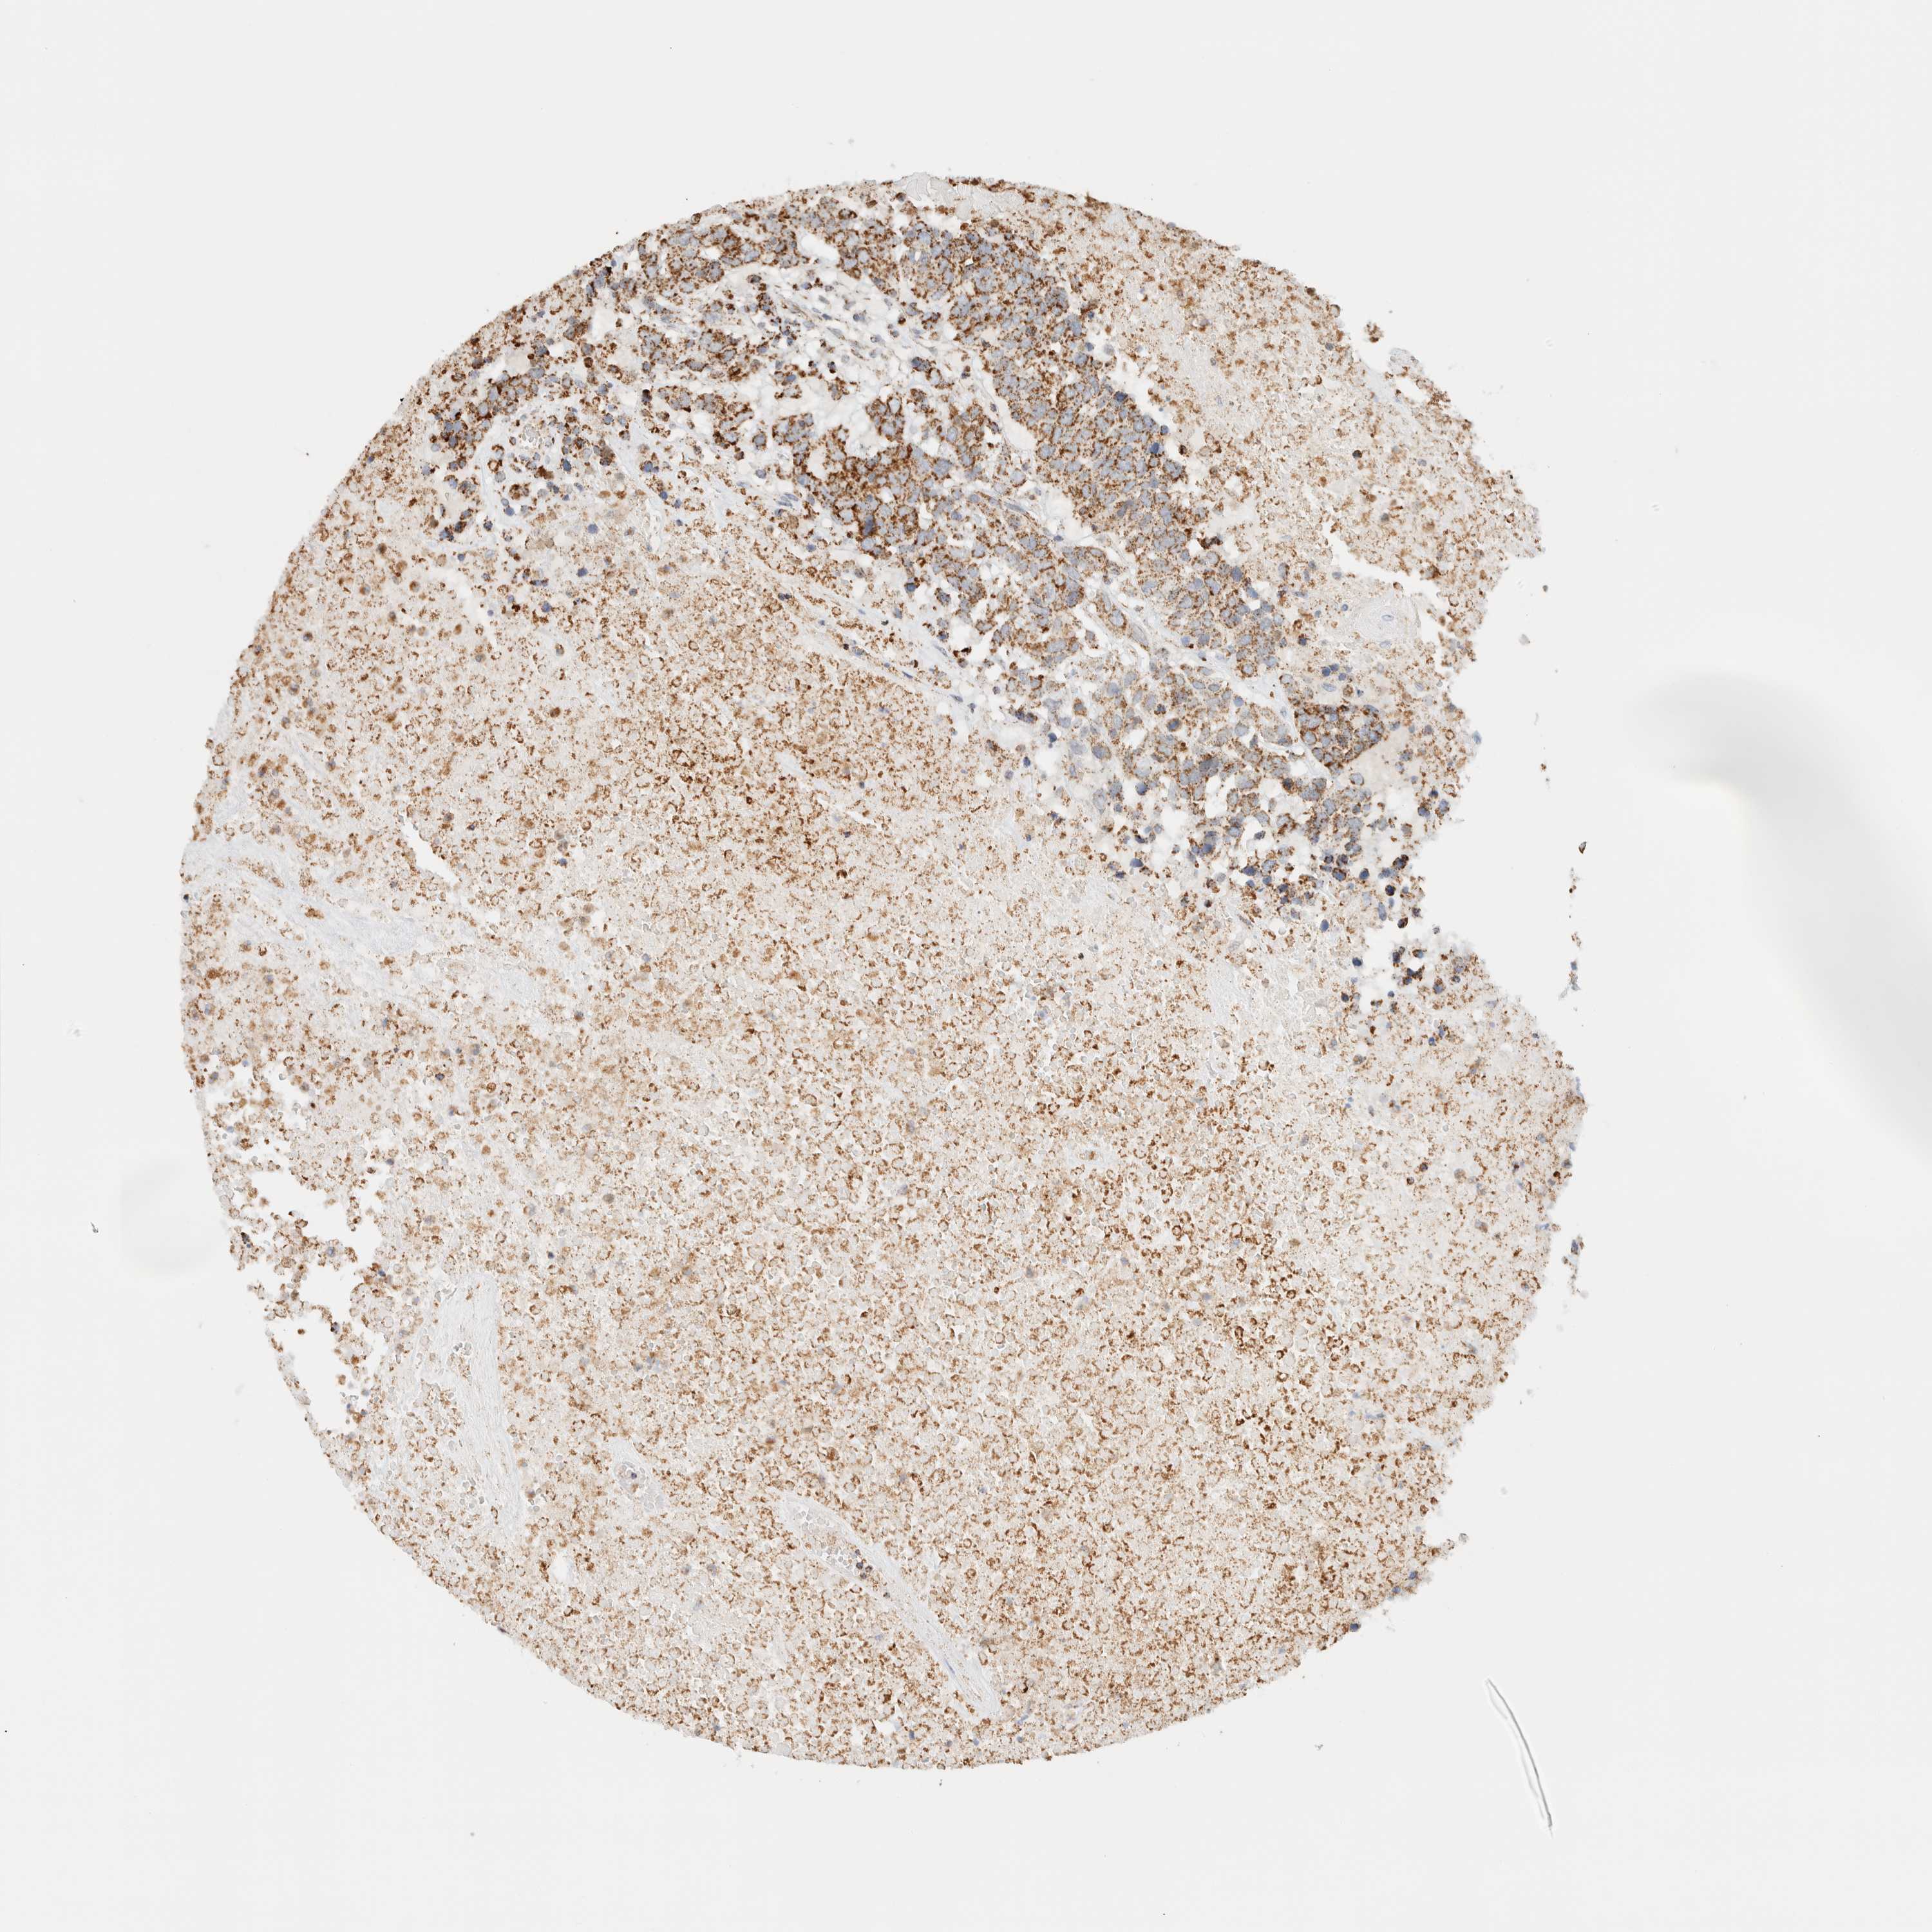

HEAD AND NECK CANCER - Protein expressioni

A mouse-over function shows sample information and annotation data. Click on an image to view it in a full screen mode. Samples can be filtered based on level of antibody staining by selecting one or several of the following categories: high, medium, low and not detected. The assay and annotation is described here.

Antibody stainingi

Antibody staining in the annotated cell types in the current human tissue is reported as not detected, low, medium, or high, based on conventional immunohistochemistry profiling in selected tissues. This score is based on the combination of the staining intensity and fraction of stained cells.

Each image is clickable and will lead to virtual microscopy that enables deeper exploration of all samples and also displays staining intensity scores, fraction scores and subcellular localization as well as patient and tissue information for each sample.

Antibody HPA023738

Antibody HPA023742

Staining

High

Medium

Low

Not detected

Intensity

Strong

Moderate

Weak

Negative

Quantity

>75%

75%-25%

<25%

None

Location

Nuclear

Cytoplasmic/membranous

Cytoplasmic/membranous,nuclear

Squamous cell carcinoma, NOS

Squamous cell carcinoma, metastatic, NOS

Adenocarcinoma, NOS